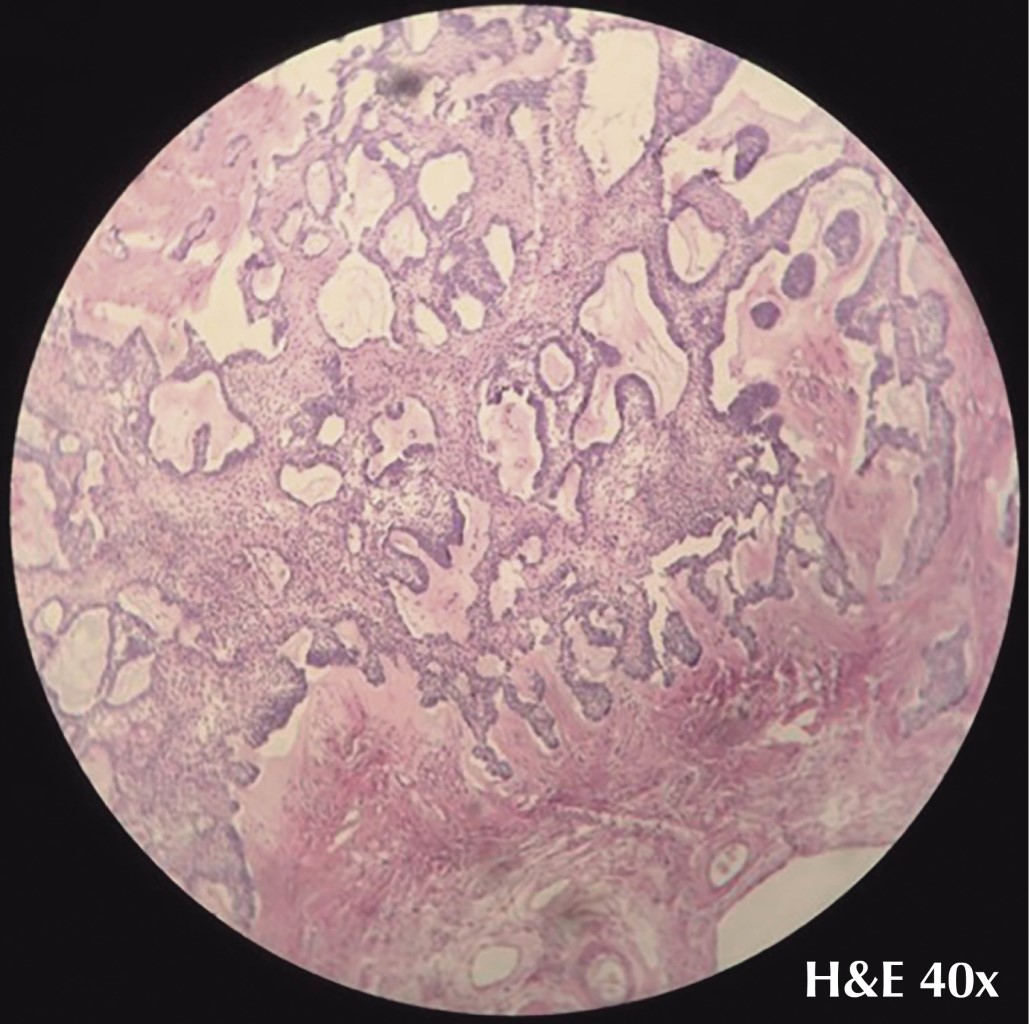

Descripción microscópica: en los cortes estudiados del tejido tumoral, observamos que está constituido por componentes epiteliales de células ameloblásticas, homogéneas en tamaño y forma en que se disponen, circunscribiendo espacios que le imprimen un patrón folicular aparentemente por retículo estrellado en otras áreas, formando partes de este tejido cordones de células ameloblásticas con patrón plexiforme (Figura 7) por cordones que se entrelazan. En alrededor de 5% se observan células del epitelio ameloblástico, con puentes intercelulares de células homogéneas en tamaño y forma, con mitosis aisladas sin atipias. En todos los cortes de cortical, el tejido óseo se encuentra íntegro y maduro por la superficie externa. El periostio muestra ligera fibrosis y cambios inflamatorios crónicos mínimos, por la cortical interna se encuentra en contacto con el tejido ameloblástico que no invade la cortical del borde quirúrgico distal de la mandíbula; éste se encuentra íntegro y muy alejado de la lesión ameloblástica.

Diagnóstico histopatológico: producto de hemimandibulectomía con ameloblastoma plexiforme y con bordes quirúrgicos libres de lesión.

Figura 7